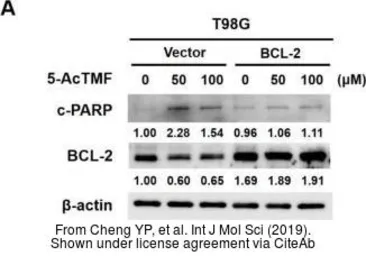

The data was published in the journal Int J Mol Sci in 2019. PMID: 31323961

The data was published in the journal Int J Mol Sci in 2019. PMID: 31323961

The data was published in the journal Int J Mol Sci in 2019. PMID: 31323961

The data was published in the journal Int J Mol Sci in 2019. PMID: 31323961